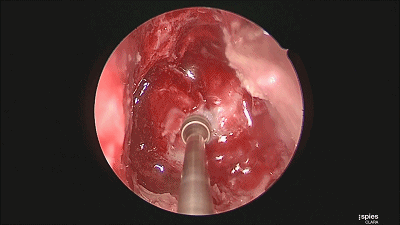

▼肿瘤切除满意后,速即纱包裹明胶海绵填塞瘤腔。

▼用纤维蛋白胶加固